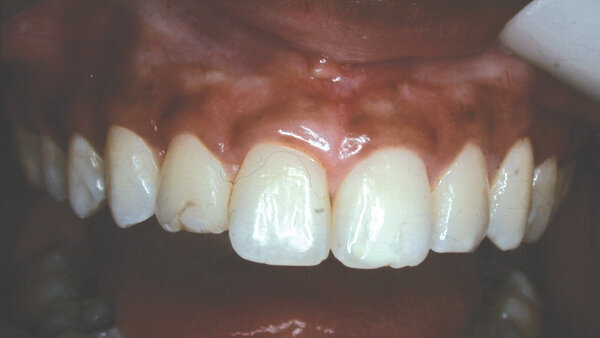

In this example case, a 19-year-old woman wanted a beautiful smile she could be proud of (Fig. 1). Initially, she presented with bleeding gingiva, but after a series of non-surgical treatments, which included oral hygiene instruction, the bleeding ceased.

Her #7 appeared to not look clean, with a worn, stained restoration labially. It also appeared short in height. The centrals had a square appearance, not the length of a normal appearing incisor, but shorter and not streamlined. The cervical line was irregular, the cuspids being higher and the centrals irregular and lower.

Fig. 1: Before, patient wanted a nicer smile. (Photo: Dr. David L. Hoexter)